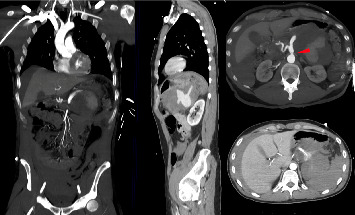

Background: Resuscitative endovascular balloon occlusion of the aorta (REBOA) is a technique aimed at temporarily interrupting or limiting blood flow through the aorta, which may be used as a bridge until definitive bleeding control by endovascular procedures or surgery. Despite the main current indication for its use is traumatic massive noncompressible torso hemorrhage, its application in end-stage nontraumatic abdominal and pelvic hemorrhage is progressively increasing. Case Presentation: A 42 year-old male patient was brought to our hospital Emergency Department with acute onset of abdominal pain, hypotension, paleness, and diaphoresis. A computed tomography (CT) was performed evidencing a voluminous retroperitoneal hematoma caused by the rupture of an unknown splenic aneurysm. Emergency open splenectomy with resection of the splenic aneurysm and evacuation of the retroperitoneal hematoma was performed, with the assistance of the REBOA technique. The endovascular balloon was positioned in the aorta, proximally to the celiac axis (Zone 1), through a percutaneous femoral access by the interventional radiologist. Intermittent aortic occlusion enabled proximal bleeding control, adequate myocardial and cerebral perfusion, and allowed surgeons to safely and successfully perform splenectomy by resecting the splenic artery at the origin. Conclusion: REBOA provides a rapid and minimally invasive hemodynamic control in severe hemorrhagic settings and its application in the initial management of nontraumatic abdominal hemorrhage should be strongly advised. Further studies with large sample size focusing on nontrauma patients are needed.